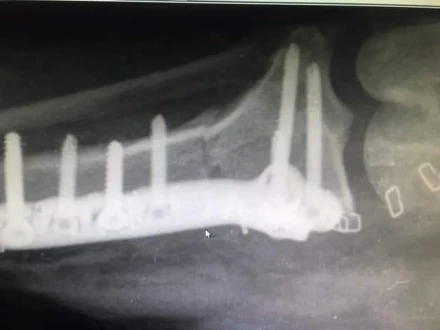

Operacje ortopedyczne:

Specjalizujemy się w szerokim zakresie operacji ortopedycznych, obejmujących leczenie złamań, problemów ze stawami, w tym operacje rekonstrukcyjne. Nasze zaawansowane techniki chirurgiczne zapewniają precyzyjne leczenie urazów i chorób układu ruchu.

Metoda TPLO